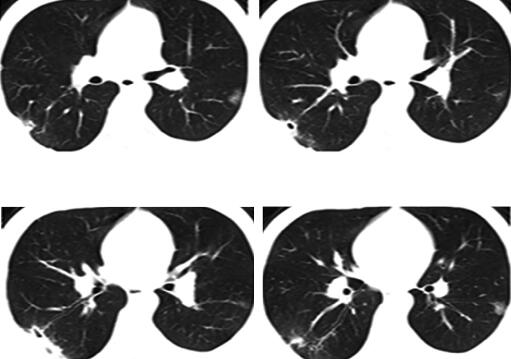

七、再问病史和检查

转入我院后详细询问病史得知:患者为高三学生,活动时间很少,虽坚持体育锻炼,但每天仍久坐10小时以上,且饮水少,经过“深挖”得知,本次发病前1个月患者曾有左下肢肿胀,自行好转,未诊治,之后一直有活动时气短,间断胸痛。因为于当地医院住院时的突出症状是寒战和高热,诊断为肺部感染,所以未问及此事。入院查体:体温36.6℃,心率74次/分,呼吸22次/分,血压140/80mmHg。神志清楚,问答合理,口唇无发绀,双肺呼吸音粗,未闻及干湿性啰音,心率74次/分,律齐,P2亢进,各瓣膜听诊区未闻及杂音,双下肢周径:髌骨上15cm:左46cm、右46cm;髌骨下10cm:左34cm、右33cm。至此真相大白,结合病史高度怀疑静脉血栓栓塞症。急查双下肢血管超声示:左侧腘静脉血栓形成;2013年3月14日CT肺动脉造影(CTPA)示:双侧肺动脉内多发充盈缺损影,以双侧肺门区为主(图4)。血D-二聚体3290μg/L。故患者明确诊断为静脉血栓栓塞症、肺血栓栓塞症、左侧腘静脉血栓形成、右下肺梗死合并感染。

图4